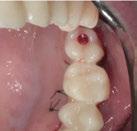

Para ilustrar el proceso, presentamos el caso de una mujer joven diagnosticada de carcinoma adenoide quístico en la región posterior del hemipaladar izquierdo (Figuras 1 y 2). El procedimiento quirúrgico realizado fue una

maxilectomía parcial que incluyó las piezas 24-26 y desde el reborde alveolar hasta la base del cráneo (Figuras 3 y 4). En este caso, la órbita y el globo ocular pudieron ser preservados. La reconstrucción inmediata se realizó mediante un colgajo de músculo temporal homolateral (Figura 5) y el defecto de la fosa temporal fue cubierto mediante una malla de titanio. Posteriormente, la paciente recibió radioterapia (Figuras 6 y 7). 2 años más tarde se diseñó un IS con anclaje en el arbotante nasomaxilar, zona subnasal izquierda

Figura 1. Imagen preoperatoria de la paciente.

Figura 2. Carcinoma adenoide quístico en región posterior del hemimaxilar izquierdo.

Figura 3. Maxilectomía parcial.

Figura 4. Defecto maxilar tras resección del tumor.